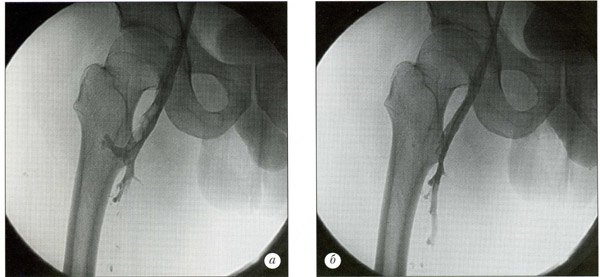

6. Флебография.

Диагностика острого венозного тромбоза в амбулаторных и в стационарных условиях базируется на оценке клинической симптоматики и результатах инструментальных методов обследования и должна осуществляться в кратчайшие сроки поскольку от быстроты определения самого факта тромбоза, его локализации, характера проксимальной части тромба зависит клинический прогноз. Во всех случаях острого венозного тромбоза обследование предпочтительно начинать с ультразвукового ангиосканирования и лишь тогда, когда визуализация затруднена (например, подвздошно-кавального сегмента) или в тех случаях, когда при наличии клиники илиофеморального флеботромбоза осуществить верификацию диагноза неинвазивно невозможно показано выполнение в экстренном порядке рентгеноконтрастного исследования. Скрининговым методом диагностики острого венозного тромбоза стал на сегодняшний день тест на Д-димер. Отрицательный его результат исключает венозный тромбоз с вероятностью 95-98% у пациентов с низким риском его возникновения.

Основной задачей хирургического лечения является предотвращение легочной эмболии. С этой целью при выявлении эмболоопасного (флотирующего) тромба в зависимости от конкретной клинической ситуации выполняют прямую или катетерную тромбэктомию, чрескожную имплантацию кава-фильтров различной конструкции, перевязку магистральных вен или пликацию нижней полой вены. Во всех остальных случаях задачи лечения решаются с помощью консервативной терапии. Также консервативная терапия в обязательном порядке должна проводиться после любого из перечисленных хирургических вмешательств.